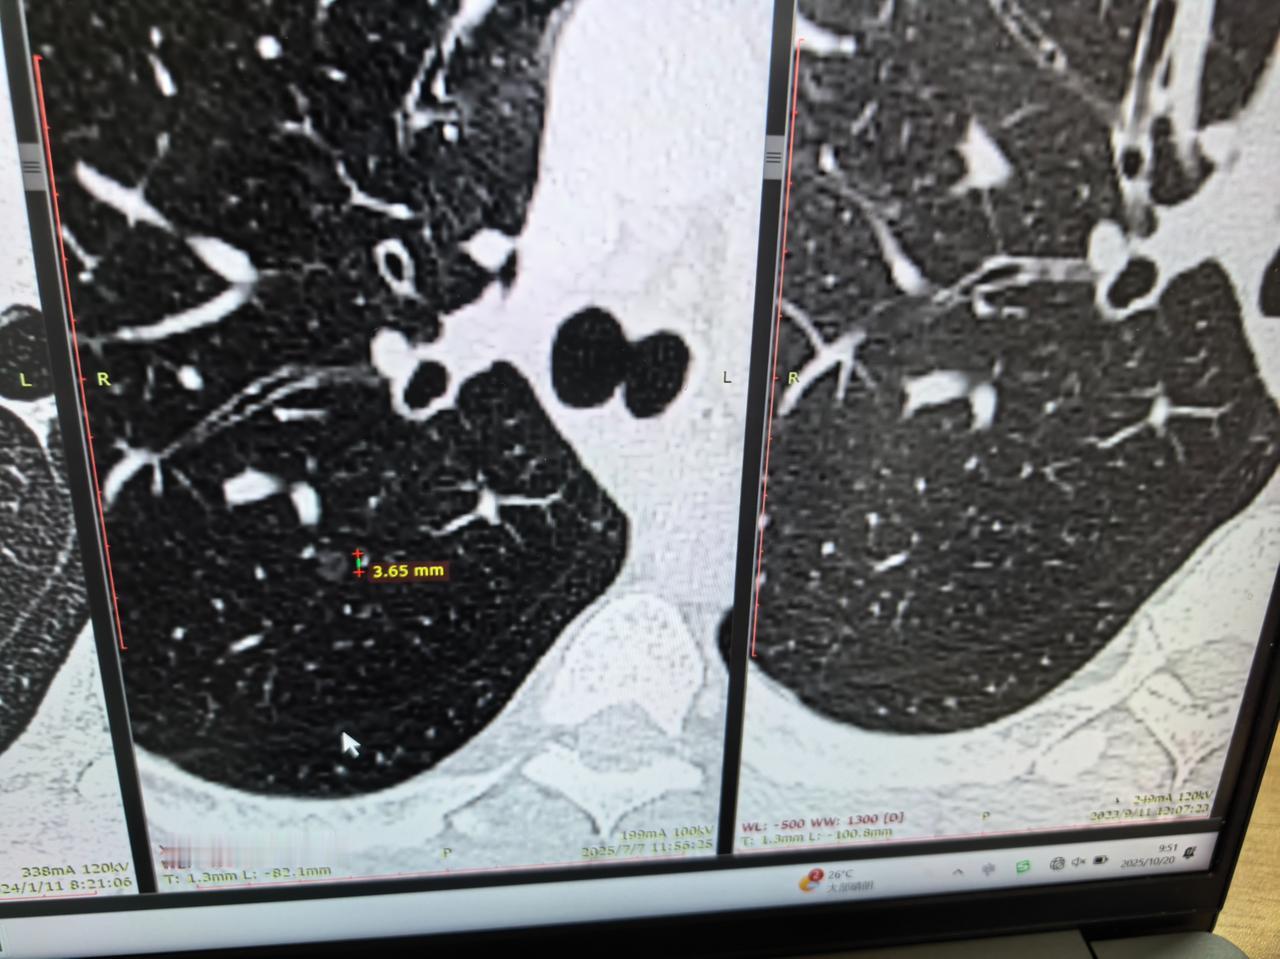

很多朋友在体检发现肺磨玻璃结节后,即使经过长期随访观察,结节大小和形态也未见明显变化,但心中始终有一个疑问:肺结节究竟是何时出现的?它是先天就存在,还是后天某个时间点才“悄然现身”的? 如果它长期保持稳定,那是否意味着它从形成之初,就进入了某种“休眠”状态? 近日,我遇到一个非常典型的临床病例,可以说为这个问题提供了生动的答案! 这位患者曾因左侧肺部结节接受过手术,术后一直坚持定期随访复查。在随访过程中,发现他原本清晰的肺部影像中,出现了一个新的、非常微小的磨玻璃结节。 也就是说,这个结节在之前的检查中是完全不存在的,属于“从无到有”的新发病灶。 令人关注的是,在随后长达一年多的严密观察中,这个新出现的磨玻璃结节并未显示出明显的增长或形态改变,始终保持着初现时的状态。从影像学的形态特征来分析,这个磨玻璃结节,首先应考虑为原位癌的可能性较大。 我们可以这样理解它的生命历程:某个时刻,肺部某些细胞在内外因素作用下发生了基因突变,开始异常增殖,形成了在影像上可见的磨玻璃结节。 然而,在它出现之后,人体强大的免疫监控系统可能识别并控制了它的进一步发展,使得这些“叛变”的细胞陷入一种被抑制的状态,既无法继续扩张,也难以彻底消失,从而进入了长期静止的病理平衡。 这个病例清晰地展示了一个肺结节完整的自然史:它并非与生俱来,而是在某个时间点新生而成;形成之后,又在免疫系统的制约下进入了长期稳定的“平台期”。 这也提示我们,对待肺部磨玻璃结节,既不必对稳定的结节过度焦虑,也不应对新发结节掉以轻心。科学的随访策略、个体化的风险评估,才是处理这类病变的核心原则。[玫瑰][谢谢]胸外科乔贵宾医生肺结节[超话]